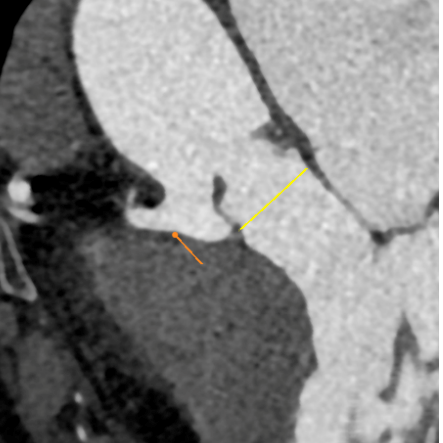

术后评估

术后彩超:峰值流速2.34m/s,跨瓣压差8.8mmHg

在多学科协作下,自贡市第四人民医院心内科已完成多例经股动脉介入主动脉瓣置换术,经过2个小时紧张有序的操作,本次手术亦取得圆满成功。术后,主动脉瓣人工瓣膜功能可,患者的平均跨瓣压差由术前的53mmHg,改善至术后的8.8mmHg, 峰值流速由术前的4.78m/s改善至术后的2.34m/s。患者获益明显, 且在苏醒后顺利转入病房,术后第2天便可下床正常活动。